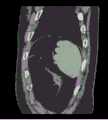

Figure 8b is a schematic representation of a sequence of CT images viewed from the sagittal plane.

fig. 8a-8c are raw three-dimensional data of sequential CT images viewed from three directions, the transverse, sagittal and coronal planes, respectively. Fig. 9a to 9c are the second binarized images obtained after the method removes the bed plate area, respectively, and it can be seen from fig. 9a to 9c that none of the skin surface contours of the human body area is damaged. Fig. 10a to 10c are respectively third binarized images obtained after filling the cavity by the method, and it can be seen from fig. 10a to 10c that the third binarized images are completely overlapped with the original three-dimensional data of the sequence CT image, and the lung region with a low threshold value is effectively filled. As can be seen from FIGS. 11a-11d, after another serial CT image is reconstructed by the method, the three-dimensional model of the skin can be fused with the third binary image and the serial CT image. And finally mapping the obtained three-dimensional model of the skin back to a 2D mode, and comparing the coincidence degree of the skin boundary in the three-dimensional model of the skin and the binary image to obtain figures 12a-12 c. In addition, the three-dimensional models of the skin of other parts of the human body obtained by the method are shown in figures 13a-13 c.